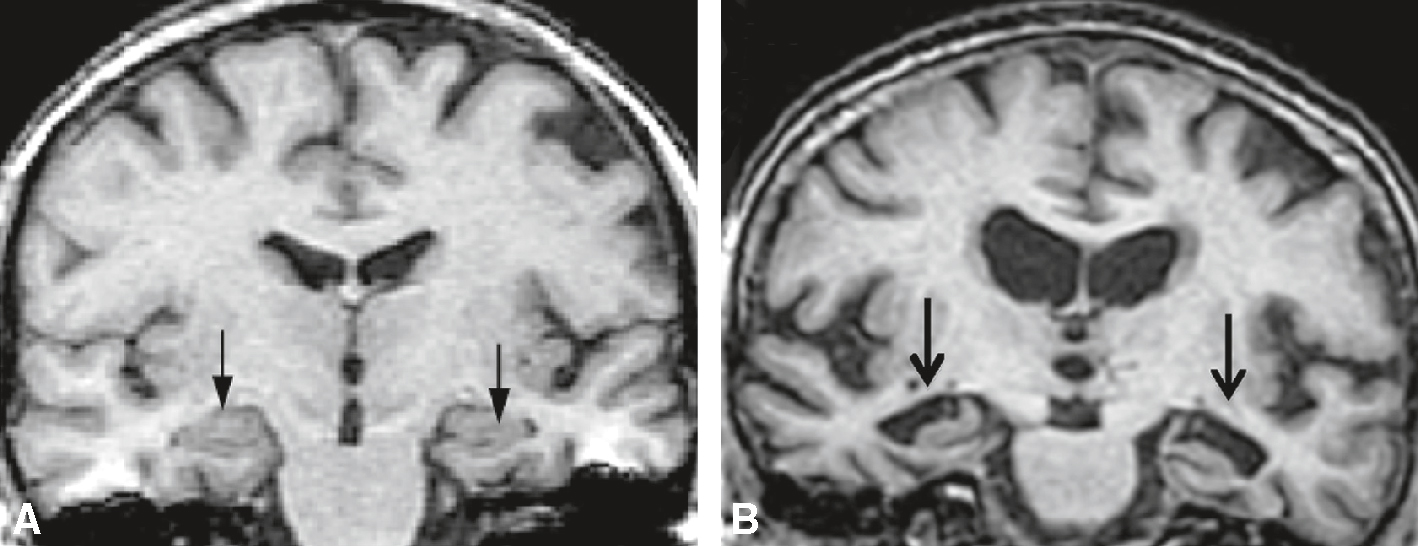

• évaluer visuellement l’atrophie des hippocampes (séquence utile : T1 coronal avec un plan de coupes perpendiculaire au grand axe de l’hippocampe) (fig. 22.4). Pour cela, il est possible de s’aider de l’échelle d’évaluation de l’atrophie des hippocampes de Scheltens (fig. 22.5). Toutefois, c’est une mesure subjective qui dépend de l’expérience du clinicien.

Fig. 22.4

IRM cérébrale pour le diagnostic positif de la maladie d’Alzheimer.

IRM en séquence pondérée T1. Les flèches localisent les hippocampes. Coupes coronales passant par le grand axe de l’hippocampe. A. Cerveau sain, pas d’atrophie des hippocampes. B. Patient Alzheimer : atrophie hippocam-pique bilatérale.L'IRM cérébrale est une technique d'imagerie médicale utilisée pour diagnostiquer la maladie d'Alzheimer. Sur l'image, on peut voir deux coupes coronales du cerveau. L'image A montre une vue antérieure du cerveau, tandis que l'image B montre une vue légèrement plus postérieure. Les flèches noires indiquent des zones spécifiques du cerveau, probablement les hippocampes, qui sont souvent affectées par la maladie d'Alzheimer. Les hippocampes sont des structures cruciales pour la mémoire et l'orientation spatiale. Dans le contexte de la maladie d'Alzheimer, ces régions peuvent montrer des signes d'atrophie, c'est-à-dire une réduction de volume, ce qui est un indicateur clé de la maladie. L'IRM permet de visualiser ces changements structurels et d'aider au diagnostic en fournissant des images détaillées des tissus cérébraux. Cette technique est non invasive et utilise des champs magnétiques et des ondes radio pour produire des images précises du cerveau. Les images obtenues peuvent révéler des anomalies qui ne seraient pas visibles avec d'autres méthodes d'imagerie, ce qui en fait un outil précieux pour les neurologues dans le diagnostic et le suivi de la maladie d'Alzheimer. En résumé, les images montrent des signes d'atrophie hippocampique, un élément diagnostique clé pour la maladie d'Alzheimer, et l'IRM est un outil essentiel pour visualiser ces changements et confirmer le diagnostic.